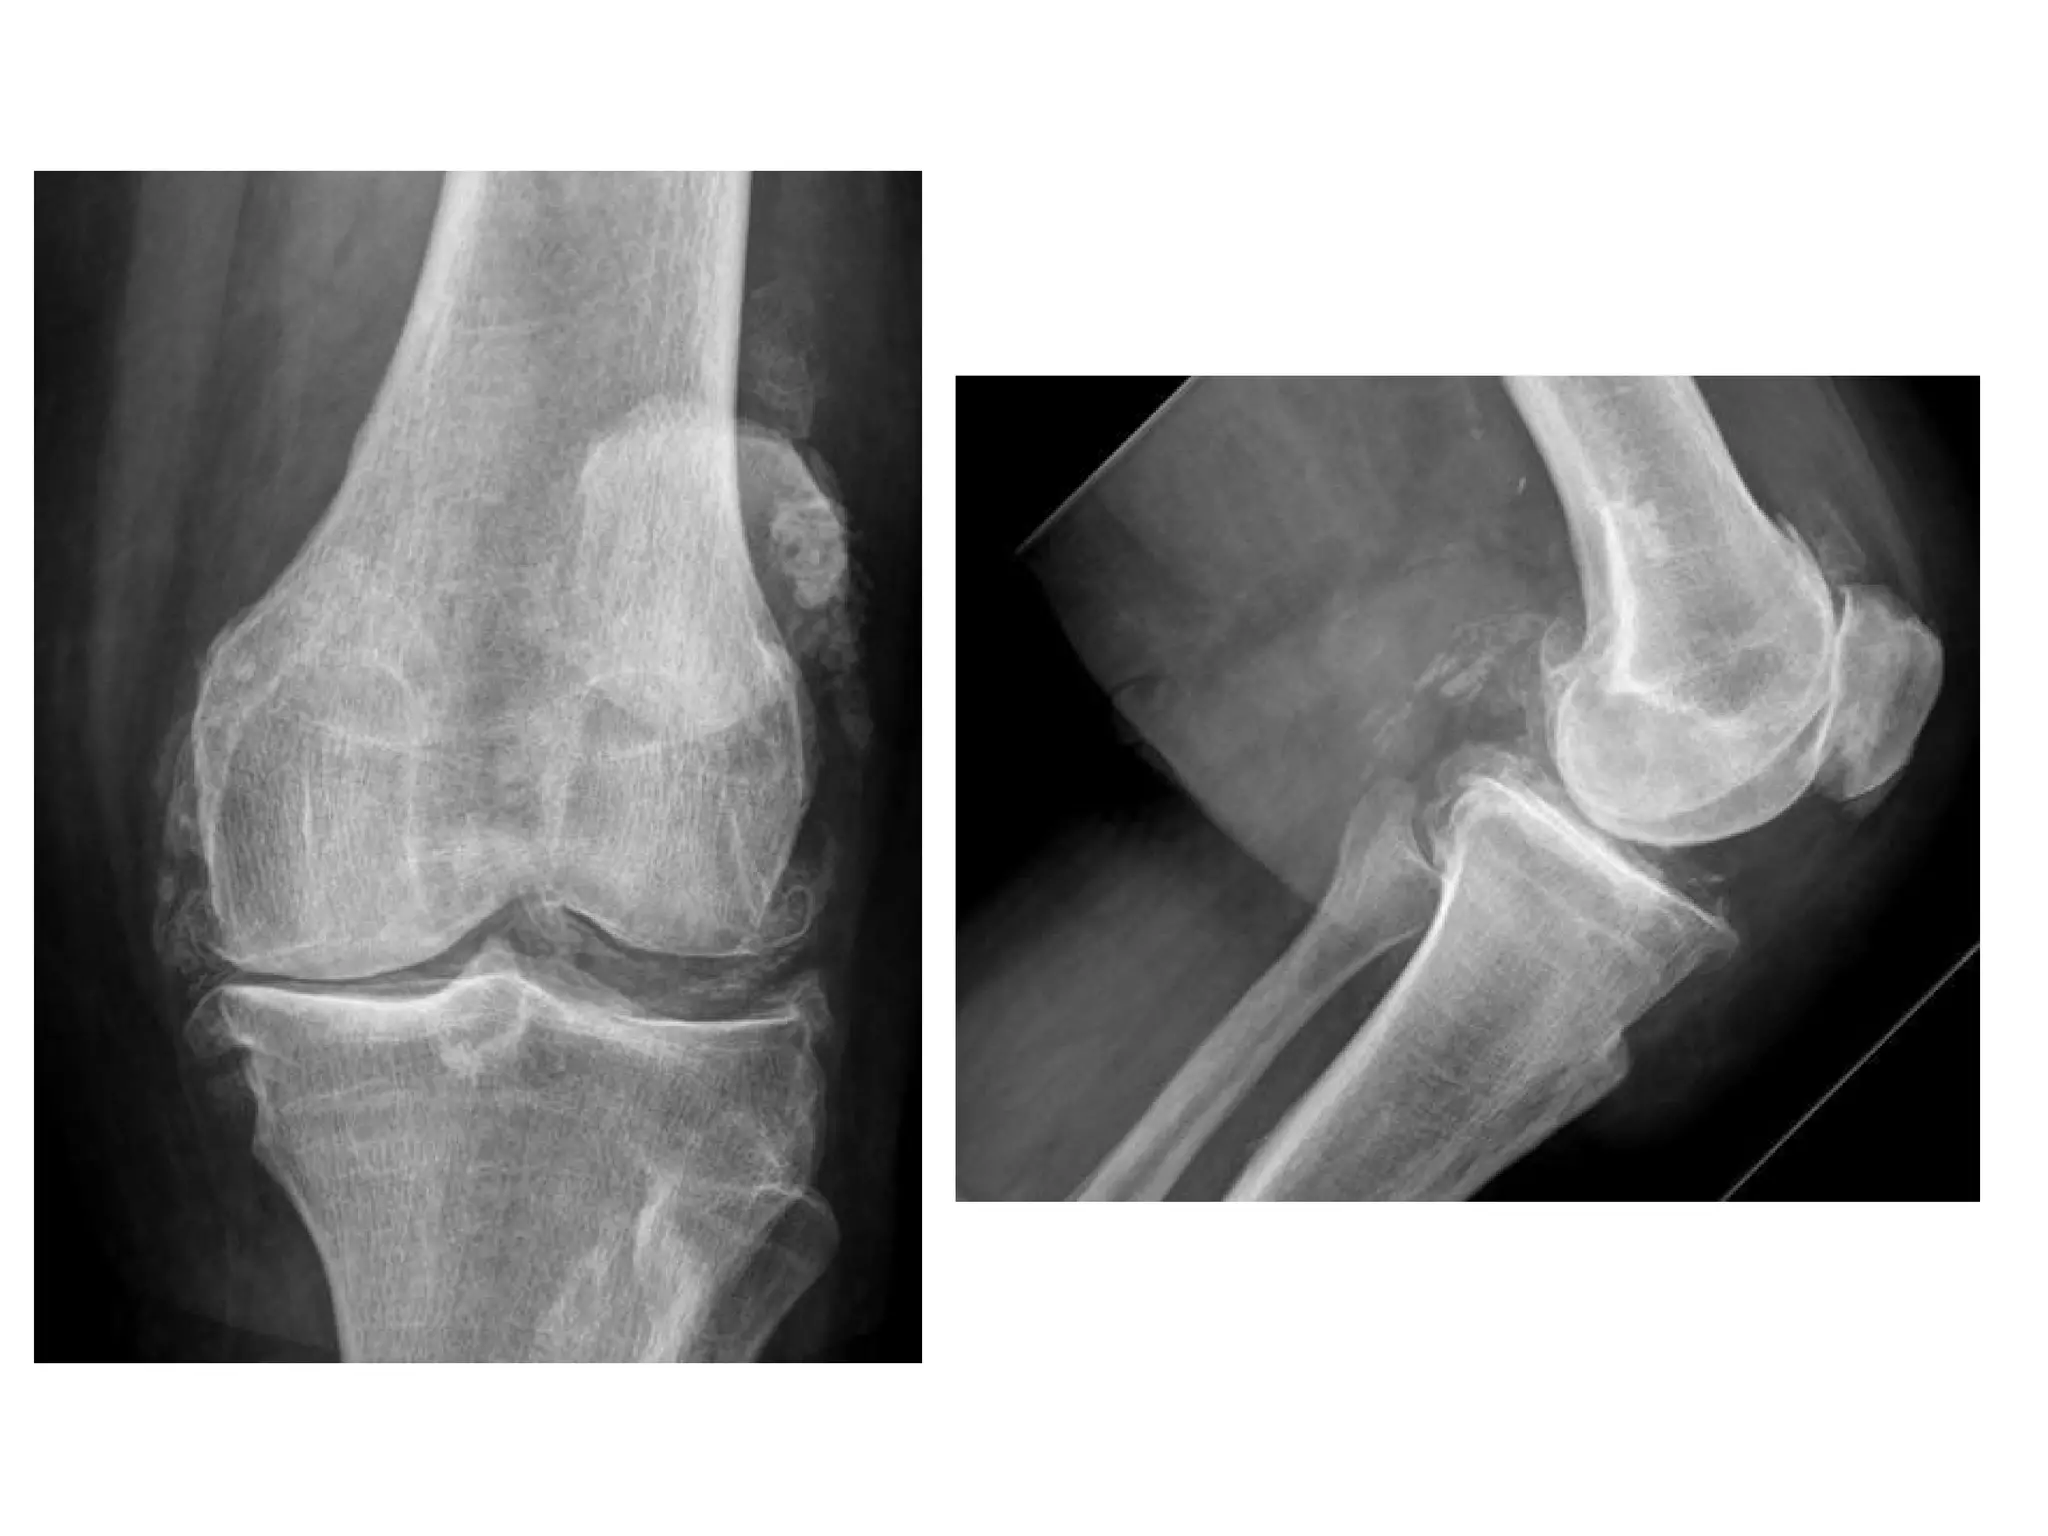

In the knees , primary OA predominately involves the medial tibiofemoral and

patellofemoral compartments , the asymmetric medial joint space loss (white

arrow) causes a varus deformity on standing radiographs , a large

osteophyte classically forms on the medial tibial articular margin (red

arrow) , subchondral sclerosis and cyst formation may also be found

Significant OA of the patellofemoral compartment , there are prominent

osteophytes (white arrows) and joint space narrowing (red arrow) , large

ossified intra-articular loose bodies are also incidentally present (blue arrow)

Severe tricompartmental osteoarthritis , joint space obliteration in the medial femoral

tibial , lateral femoral tibial and patellofemoral compartments ; varus angulation and

lateral subluxation of the tibia and osteophyte formation